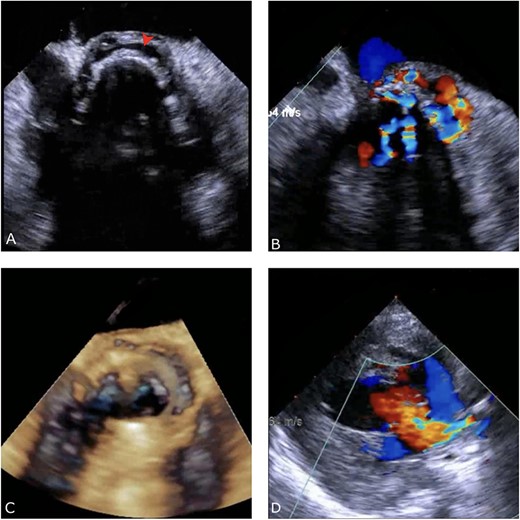

A thorough cardiovascular examination was performed, which revealed normal prosthetic valve clicks and a grade 3 ejection systolic murmur in the right second parasternal space. Further investigations included a transesophageal echocardiogram (TEE), which showed a paravalular anechoic free space around the prosthetic mechanical aortic valve with paravalular leakage and regurgitant flow with dehiscence of the prosthesis causing aortic stenosis (Fig. 1). A computed tomography (CT) scan was also performed to rule out aortic calcification, which revealed a normally seated aortic valve prosthesis with no visualization of the paravalular free space (Fig. 2). During the preoperative workup, blood cultures showed bacterial growth of Brucella melitensis. A multidisciplinary team approach was initiated, and the patient was started on antimicrobial therapy with gentamicin, doxycycline and rifampin. However, due to the patient developing abnormally high levels of Aspartate aminotransferase (AST) and Alanine aminotransferase (ALT), which is a side effect of rifampin, the regimen was changed to ceftriaxone, doxycycline and trimethoprim/sulfamethoxazole.

Preoperative TEE: (A) Red arrow pointing at a paravalvular anechoic free space around the prosthetic mechanical aortic valve. (B) Echo image showing paravalvular regurgitation and leakage around the prosthetic mechanical valve. (C) 3D reconstructive echocardiography image showing paravalvular free space around the aortic mechanical valve at 3–9 o’clock with aneurysmal echo free space at the aortomitral curtain protruding into left atrium. (D) Aortic prosthetic mechanical valve dehiscence causing aortic stenosis with moderate paravalvular regurgitation.